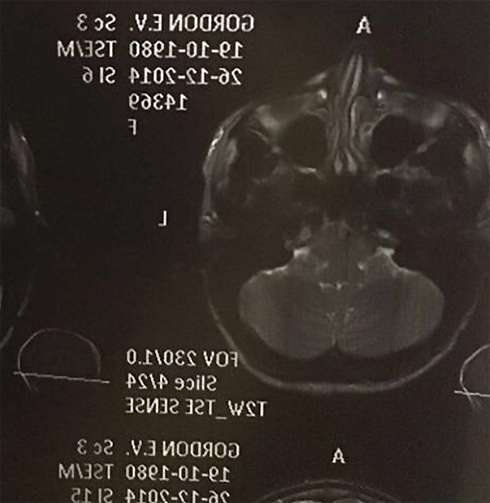

«Это я без фотошопа;))) и мой кривой клювик;))) я давно, вы знаете, мечтала исправить перегородку. Я обошла всех врачей и ездила за границу с этим вопросом… Было дико страшно и, конечно, это не ногти сделать… Но я нереально счастлива, что отныне буду сниматься не только с правой щеки;)) и, рабочие, стороны у меня теперь две;)) к сожалению, реабилитация в ринопластике не два дня… Но я столько ждала, что этот месяц с вашей поддержкой переживу спокойно;))» (здесь и далее орфография и пунктуация авторов сохранены, — прим. WomanHit.ru), — сообщила подписчикам Гордон. При этом она опубликовала рентгеновский снимок своего носа.